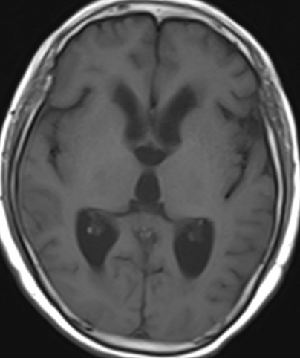

2013-8-2 CT

腰穿脑压240